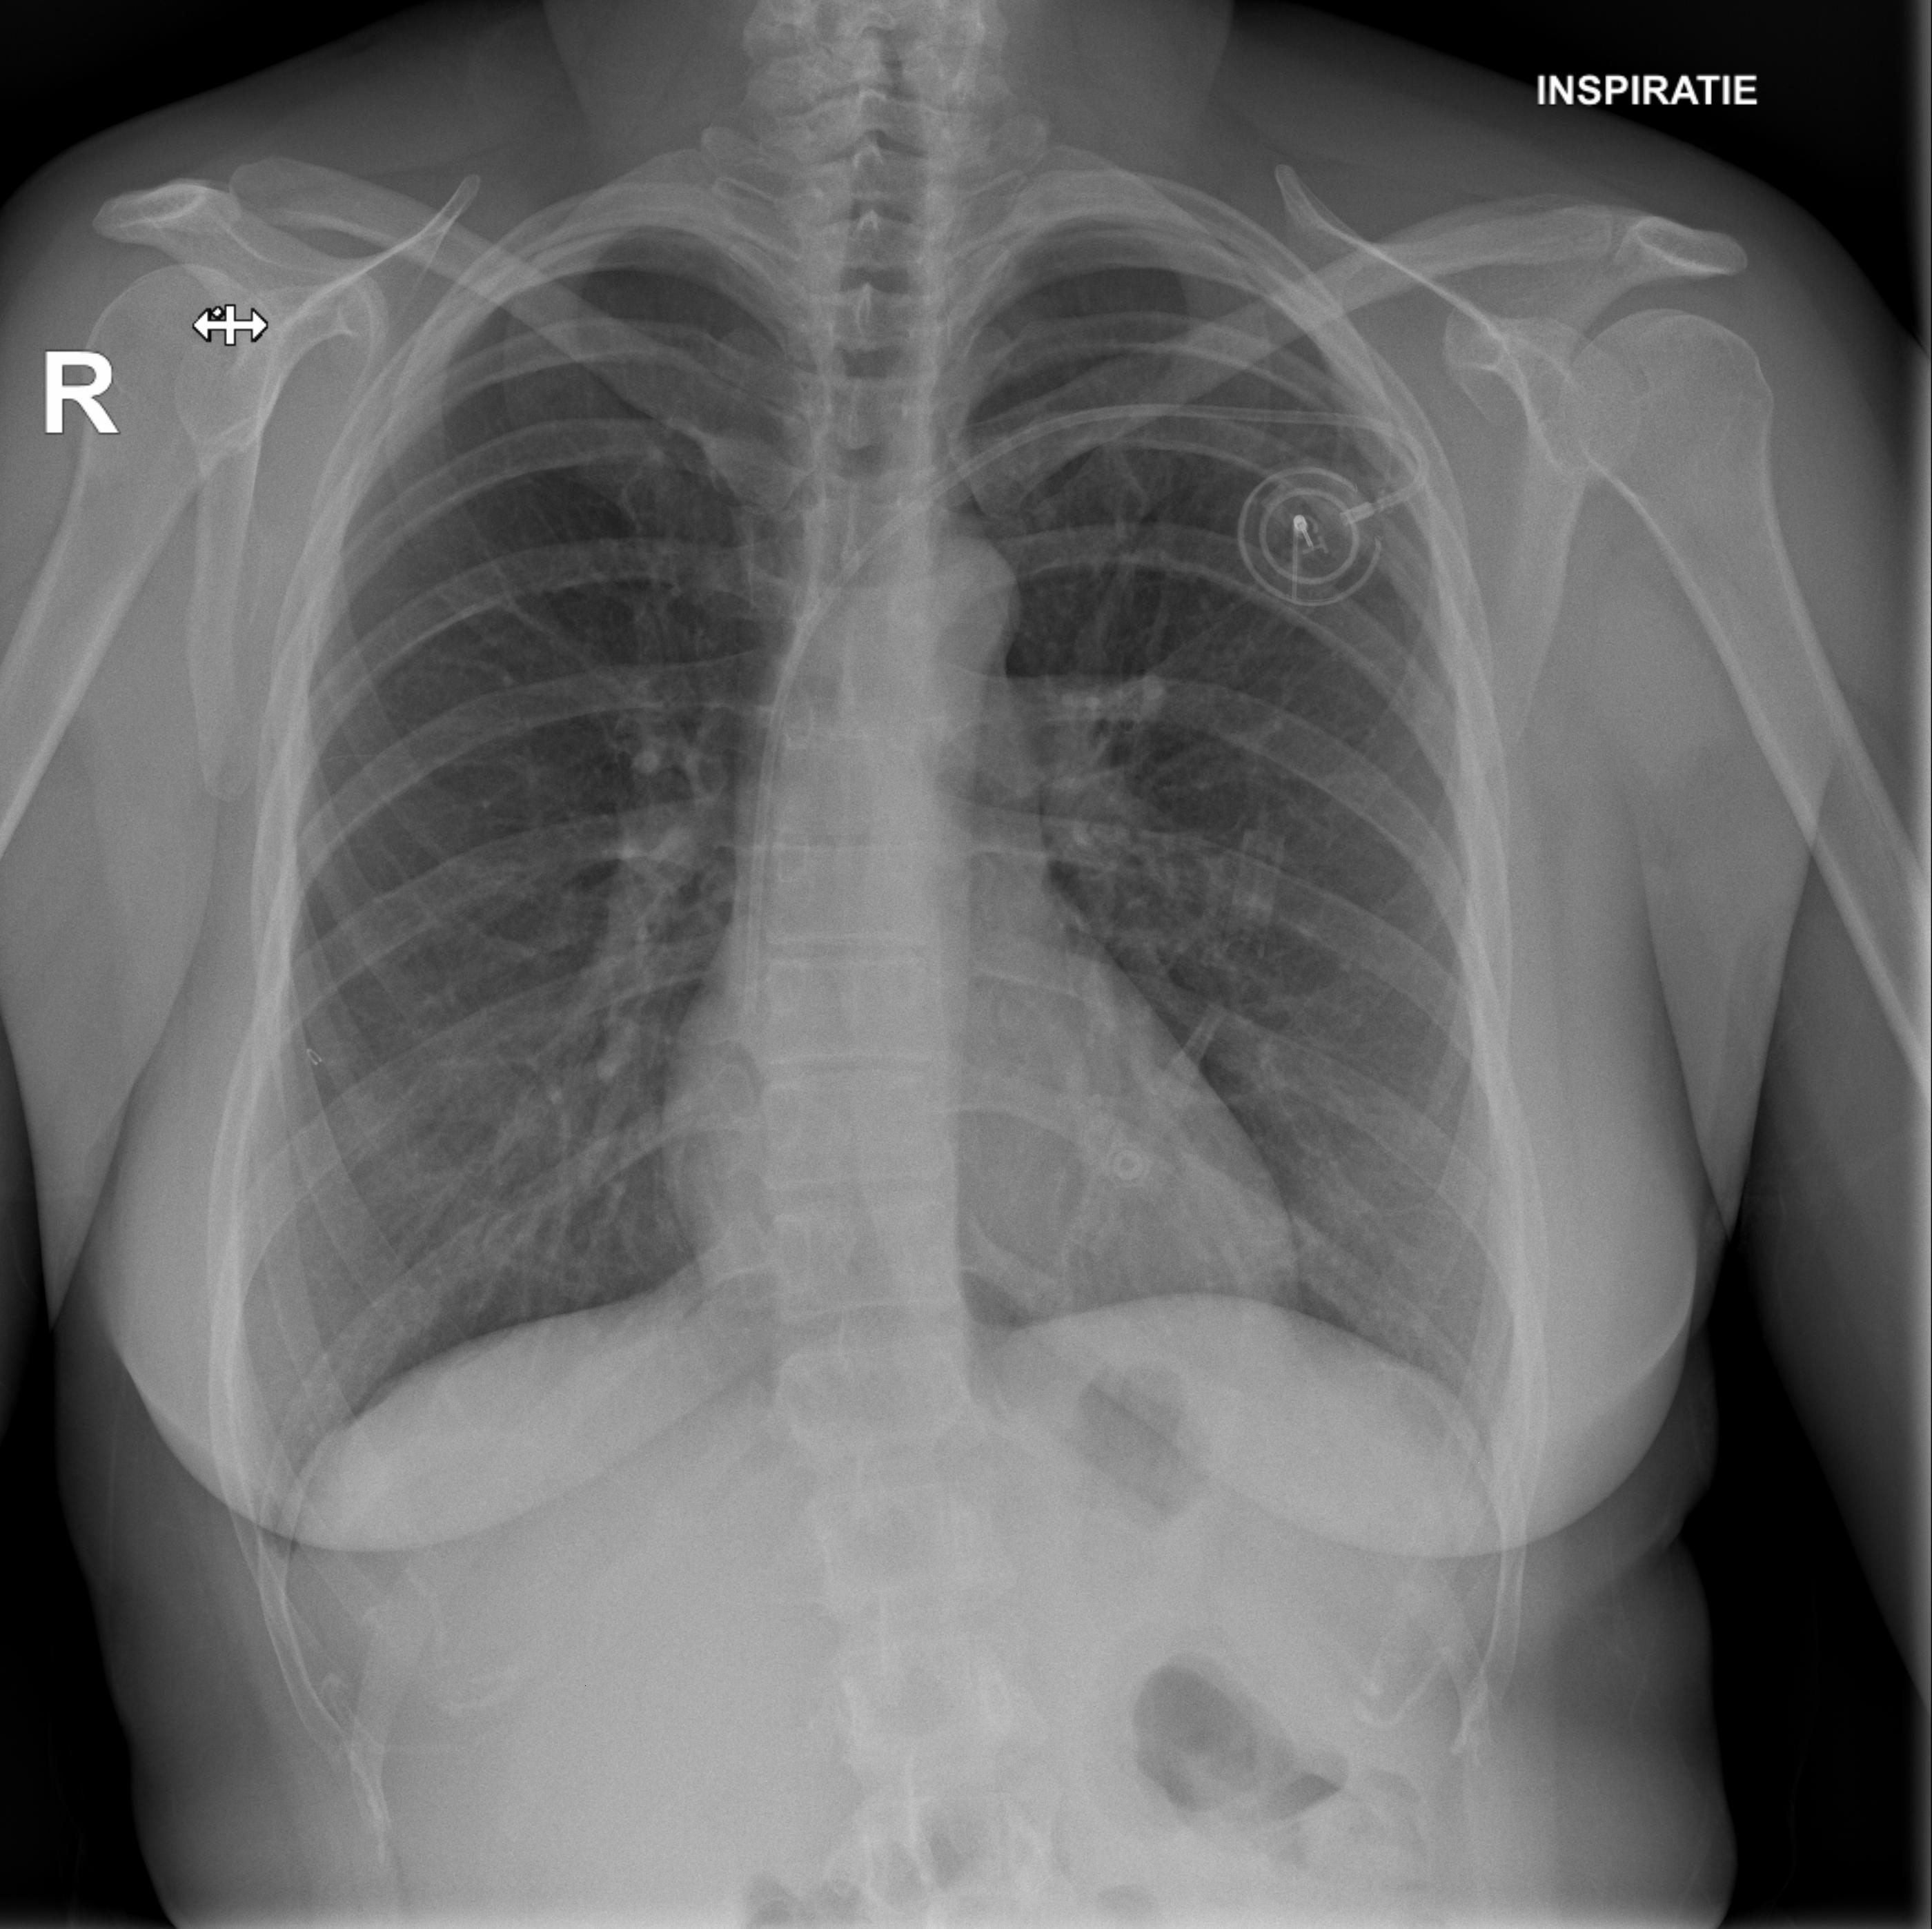

Chemotherapy day (finally) arrived: the sooner I started, the better, obviously. Not sure what happened on the day, but I fainted while getting ready. The pain from the port surgery, the tiredness, the stress of it all, I just went down on my face. My oncologist suspected a pneumothorax (a collection of air outside the lung but within the pleural cavity) so I was sent to radiology for some x-rays.

They checked my lungs during inspiration (first image) and expiration (second image): you can clearly see Portia with the catheter getting into my subclavian vein.

Luckly enough, I didn’t have a pneumothorax, so we went ahead with chemotherapy.